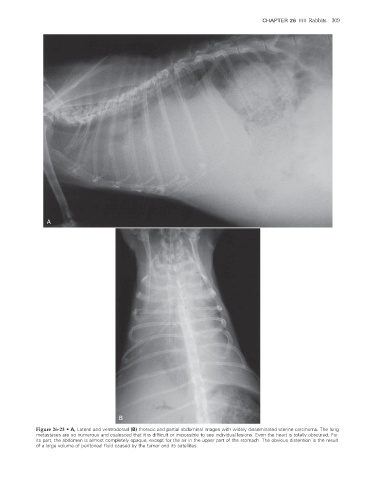

Figure 26-23 • A, Lateral and ventrodorsal (B) thoracic and partial abdominal images with widely disseminated uterine carcinoma. The lung

metastases are so numerous and coalesced that it is difficult or impossible to see individual lesions. Even the heart is totally obscured. For

its part, the abdomen is almost completely opaque, except for the air in the upper part of the stomach. The obvious distention is the result

of a large volume of peritoneal fluid caused by the tumor and its satellites.